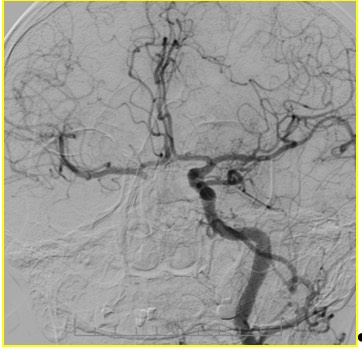

1700. На представленной ангиографии интракраниального отдела левой вса можно предположить